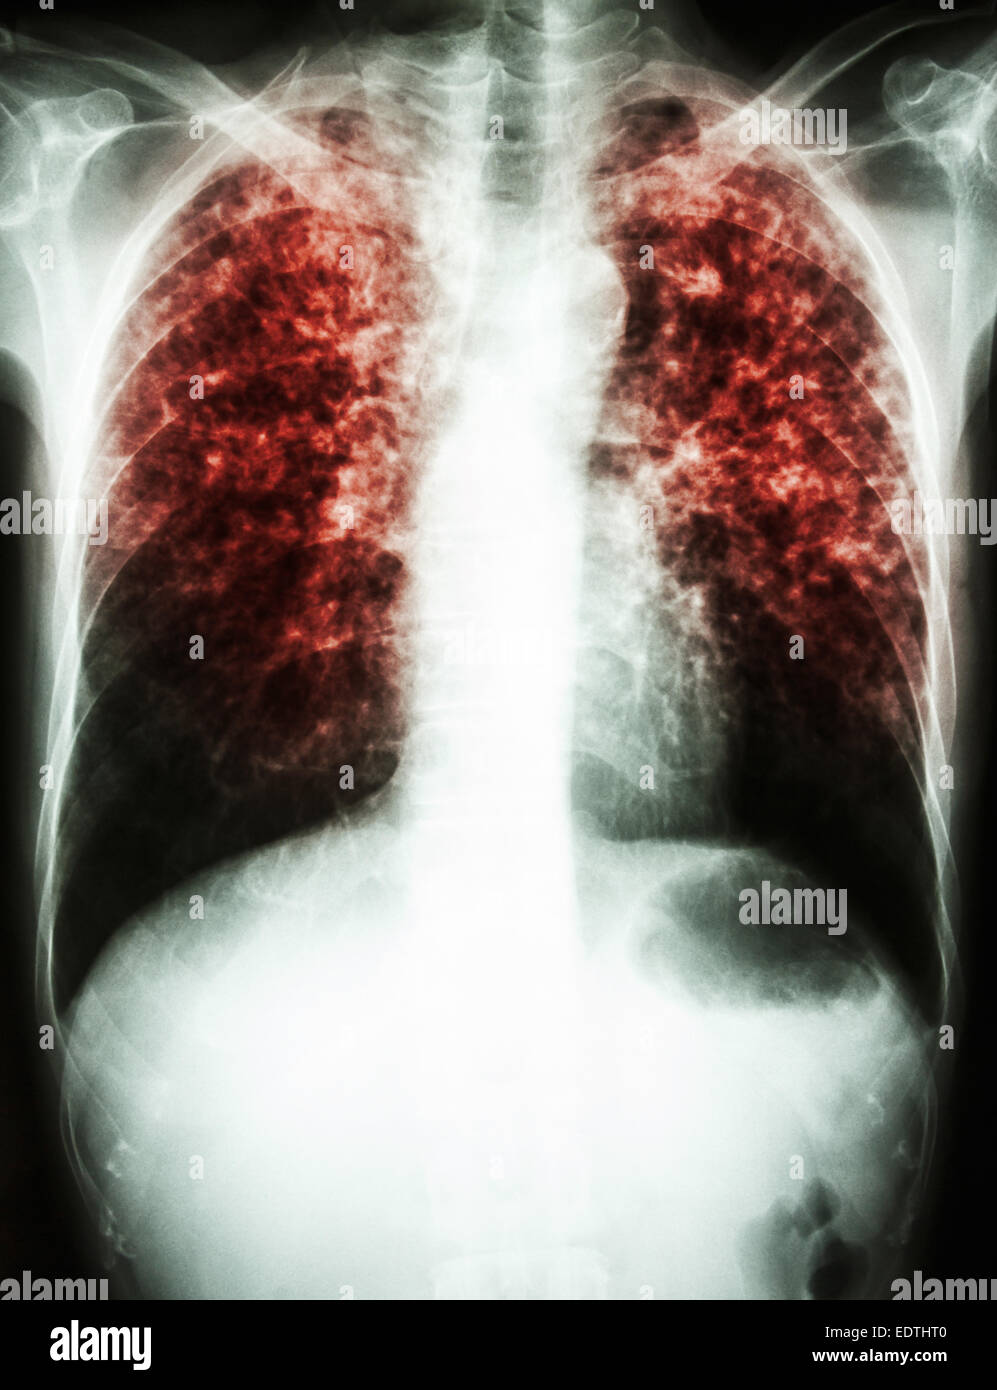

From www.alamy.com

"Pulmonary tuberculosis" Film chest xray show interstitial What Does A Chest X-Ray Show If You Have Tb Your health care provider will do other tests to determine if you have inactive tb or active tb. A positive test result for tb infection means you have tb germs in your body. If you have symptoms of active tb (see tuberculosis) in your lungs, you should be offered tests by a healthcare professional. This may show signs of cavitation,. What Does A Chest X-Ray Show If You Have Tb.

film chest xray show interstitial infiltrate both lung due to What Does A Chest X-Ray Show If You Have Tb Your health care provider will do other tests to determine if you have inactive tb or active tb. This may show signs of cavitation, pleural effusion, mediastinal or hilar lymphadenopathy, or parenchymal infiltrates,. A positive test result for tb infection means you have tb germs in your body. If you have symptoms of tuberculosis (tb), tests you may have include:. What Does A Chest X-Ray Show If You Have Tb.